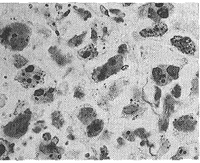

2.3 AgNORs颗粒计数测定 组织切片行银染,细胞核呈淡黄色,AgNORs呈棕褐色颗粒状。光镜下,Ⅰ组AgNORs颗粒多为弥散型,少见单一型和混合型。从第Ⅱ组至Ⅳ组,混合型和单一型逐渐增多,第Ⅳ组主要 表现为单一型(图3、4、5)。从第Ⅰ组至第Ⅳ组,胞核的数目,颗粒的面积、周长、平均直径均依次增大,而其它各参数均依次减小(表2)。以上参数各用药组与对照组比较:Ⅱ与Ⅰ比,差异有显著性(P<0.05);Ⅲ、Ⅳ与Ⅰ比,差异有显著性(P<0.01)。各用药组之间比较:Ⅲ、Ⅳ与Ⅱ比,差异有显著性(P<0.01);Ⅳ与Ⅲ比,差异有显著性(P<0.05)。这说明,从Ⅰ组至Ⅳ组,平均每个视野胞核的数目增多,胞核的体积就相对缩小,肿瘤细胞生长受到抑制,而AgNORs颗粒的体积逐渐增大,AgNORs计数逐渐减小。同样联合用药效果最好,单用紫杉醇组较好。

图3 .Ⅰ组肿瘤结节组织切片,AgNORs颗粒多而小,多为弥散型 银染 ×1165

Fig 3 Histological section of tumor for group Ⅰ (The AgNORs granule increased in amount but minified, and appeared diffused-type in most cases. Silver staining ×1165)

图4 .Ⅲ组肿瘤结节组织切片,AgNORs颗粒少而大,弥散型 银染 ×1165

Fig 4 Histological section of tumor for group Ⅲ (The AgNORs granule decreased in amount but magnified, and appeared mixed-type in most cases. Silver staining ×1165)